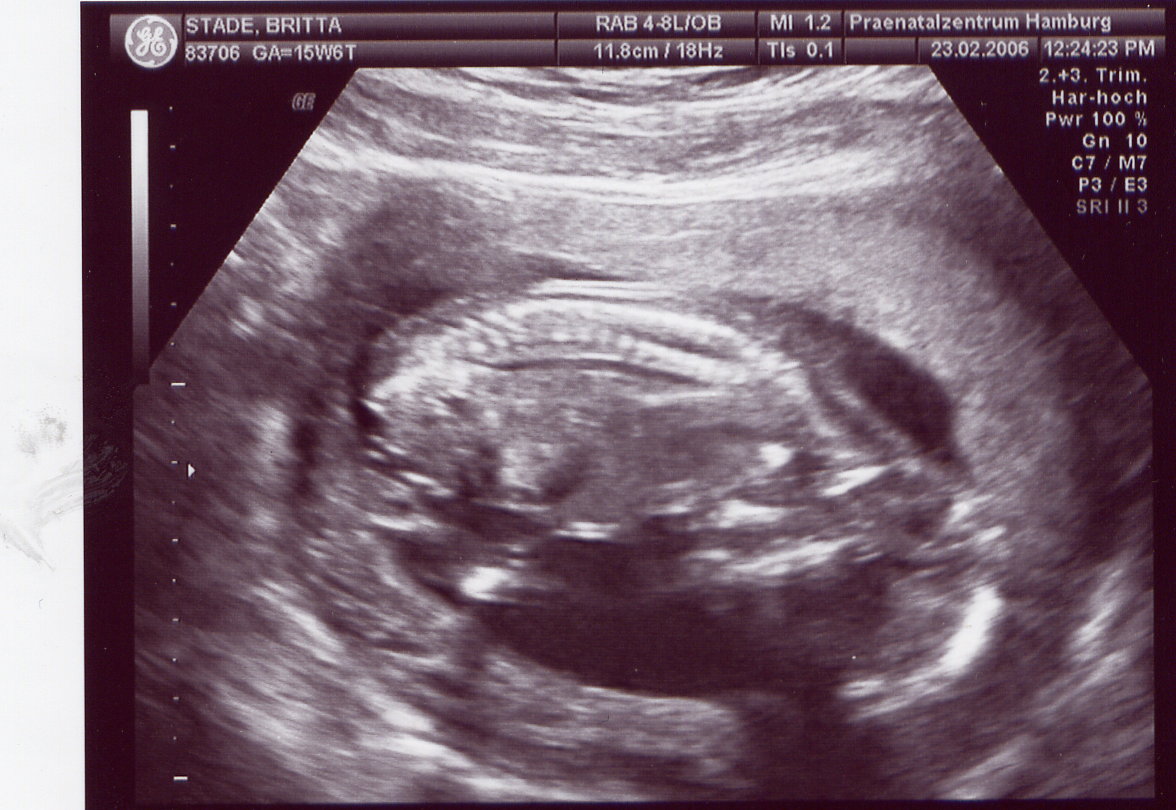

Das Organscreening wird wiederum aufgrund meines Alters gemacht und weil ich durch künstliche Befruchtung schwanger geworden bin. Mein Arzt geht da lieber auf Nr. sicher. Ihr wißt doch, daß einem nur noch 3 US-Bilder zur Verfügung stehen und ich hab doch schon 5, zwei davon wurden mir geschenkt

Aber leider sind die US-Bilder von meinem Haus-Gyn so dunkel, daß diese ganz schlecht zu scannen sind, wie ihr vielleicht schon gesehen habt. Habt ihr sonst einen Tip?

23.02.06 FU / Ergebnis OK